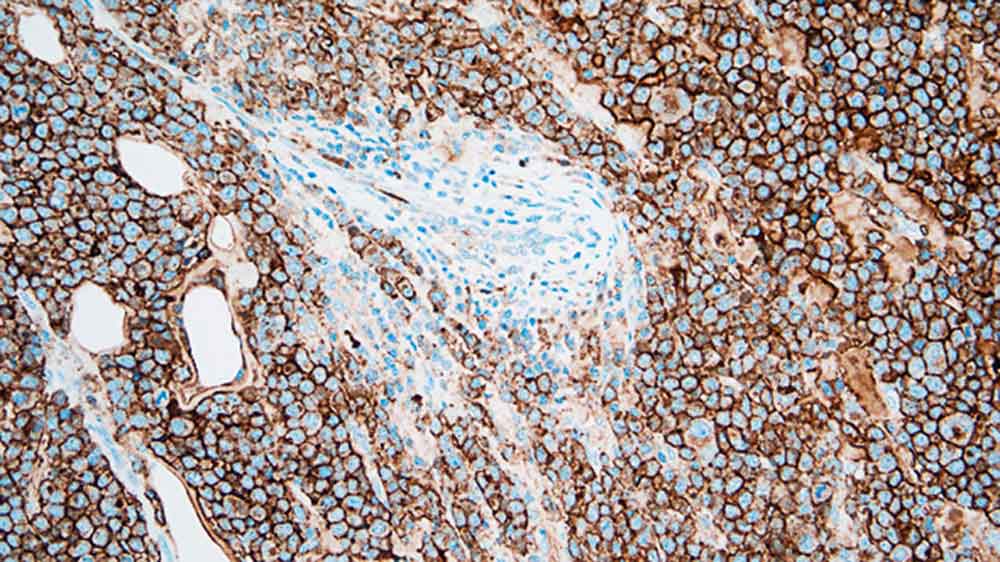

Plasmacytoma: immunohistochemical staining for CD138. Note the intense membrane staining of tumor cells. CD138: clone MI15

La molécule CD138 est une glycoprotéine à héparane sulphate transmembranaire exprimée à des stades spécifiques de la différenciation des cellules lymphoïdes normales, comme les cellules pré-B, les lymphocytes B immatures et les cellules plasmatiques productrices d'Ig, et également exprimée dans les épithéliums simples et stratifiés. La perte de l'expression de la CD138 par les cellules atypiques a été décrite comme un évènement précoce de la carcinogenèse du col de l'utérus, alors que l'expression de l'antigène 138 est intimement associée à la préservation de la morphologie et de la différenciation de l'épithélium. Cependant, l'utilité principale de la CD138 en immunohistochimie est la quantification des cellules plasmatiques.